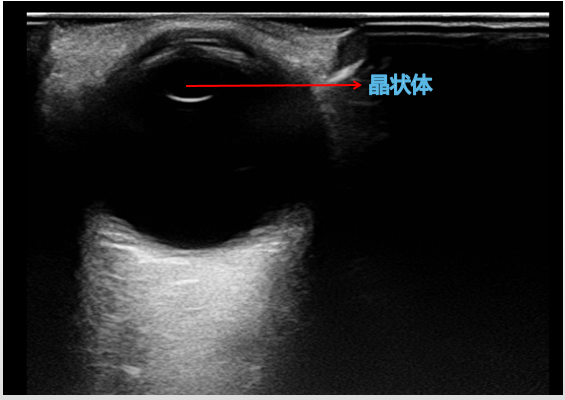

图 4 正常晶状体二维超声表现

图片来源:作者提供